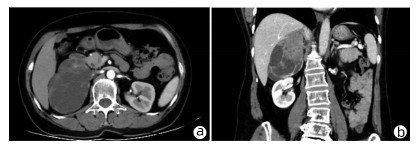

Solitary fibrous tumor of the liver: A case report

Xuecheng LI, Ying FAN, Shuodong WU

2022, 38(3): 632-633. DOI: 10.3969/j.issn.1001-5256.2022.03.026

Abstract(917) HTML (232) PDF (2657KB)(72)

Abstract: